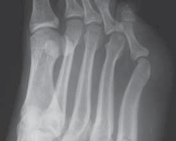

Question 29

Which of the following best describes a Jones fracture? tarsometatarsal joint. the fourth–fifth intermetatarsal articulation. fourth–fifth intermetatarsal articulation. fifth intermetatarsal articulation.

Explanation:

Fracture at the metaphyseal–diaphyseal junction of the fifth metatarsal at the level of the fourth–fifth intermetatarsal articulation. Fractures of the base of the fifth metatarsal are common. They are classified into zones according to location: Zone 1 – Proximal metaphyseal fracture of the fifth metatarsal at the level of the tarsometatarsal joint Zone 2 – Fracture at the metaphyseal–diaphyseal junction of the fifth metatarsal at the level of the fourth–fifth intermetatarsal articulation Zone 3 – Fracture at the proximal diaphysis of the fifth metatarsal distal to the level of the fourth–fifth intermetatarsal articulation The zone 2 injury is also known as a Jones fracture, after Sir Robert Jones. 216